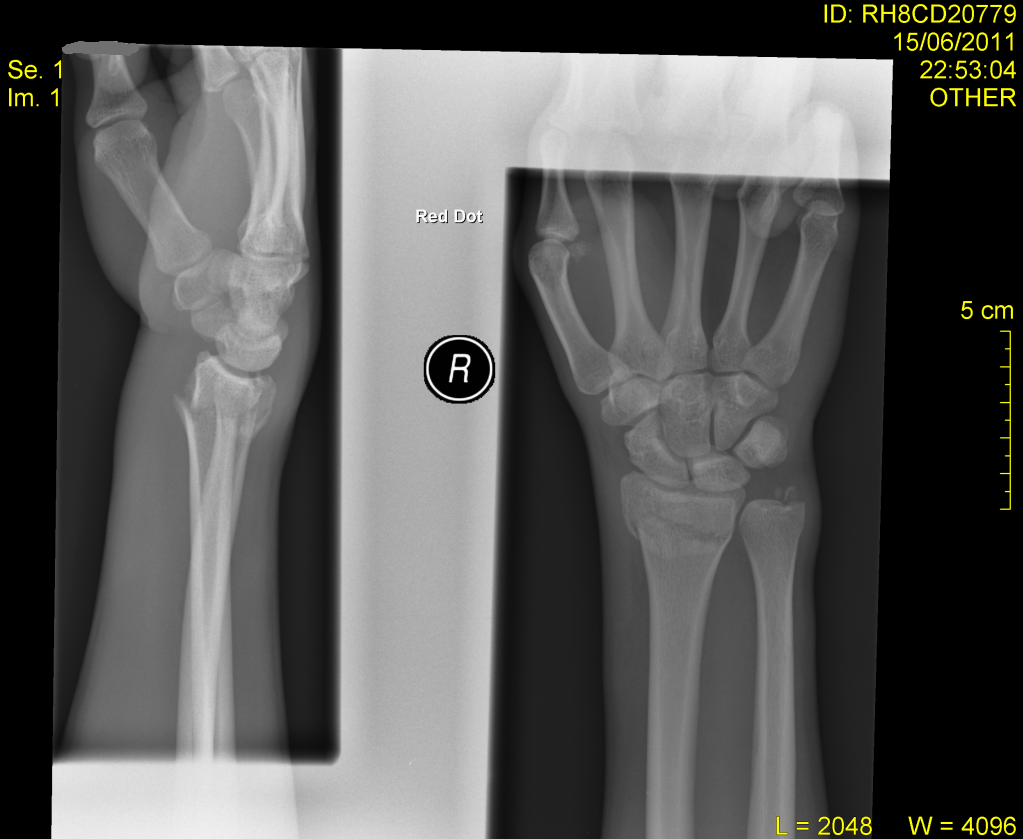

This is my brothers wrist from a few years ago took him a while in plaster and then half as long again to build up the muscle. He said a powerball helped loads.

left one looked like this:

Dislocated, end snapped off ulner, radius shattered, bone graft from hip, 9 months off work, career change due to injury, now won't rotate more than 90 degrees, 10 years ago now numb most mornings.

[img][url= http://farm8.staticflickr.com/7212/7202710598_23724310ed.jp g" target="_blank">http://farm8.staticflickr.com/7212/7202710598_23724310ed.jp g"/> [/img][/url][/img]